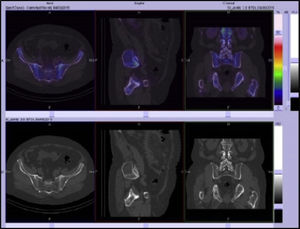

In the bone scan images there was no sign of articular pathological uptake (Fig. 3). Multimodality SPECT/CT tomographic images were then acquired (Figs. 4 and 5), which were used both for qualitative visual analysis of the sacroiliac joint, and for quantitative analysis which permitted the obtainment of indicators of the sacroiliac-promontory. In visual analysis calcification of the anterior common vertebral ligament was detected, together with absence of sacroiliac uptake. With this information and inferior promontory-sacroiliac indicators below the established cut-off level for diagnosis of sacroiliitis, diagnosis of ankylosing spondylitis was excluded, with support for the diagnosis of Forestier's disease.

SPECT/CT slice images in axial, sagittal and coronal planes with low uptake of the radiopharmaceutical in sacroiliac joints. Sacroiliac/promontory values below cut-off level established for diagnosis of sacroiliitis.7,8